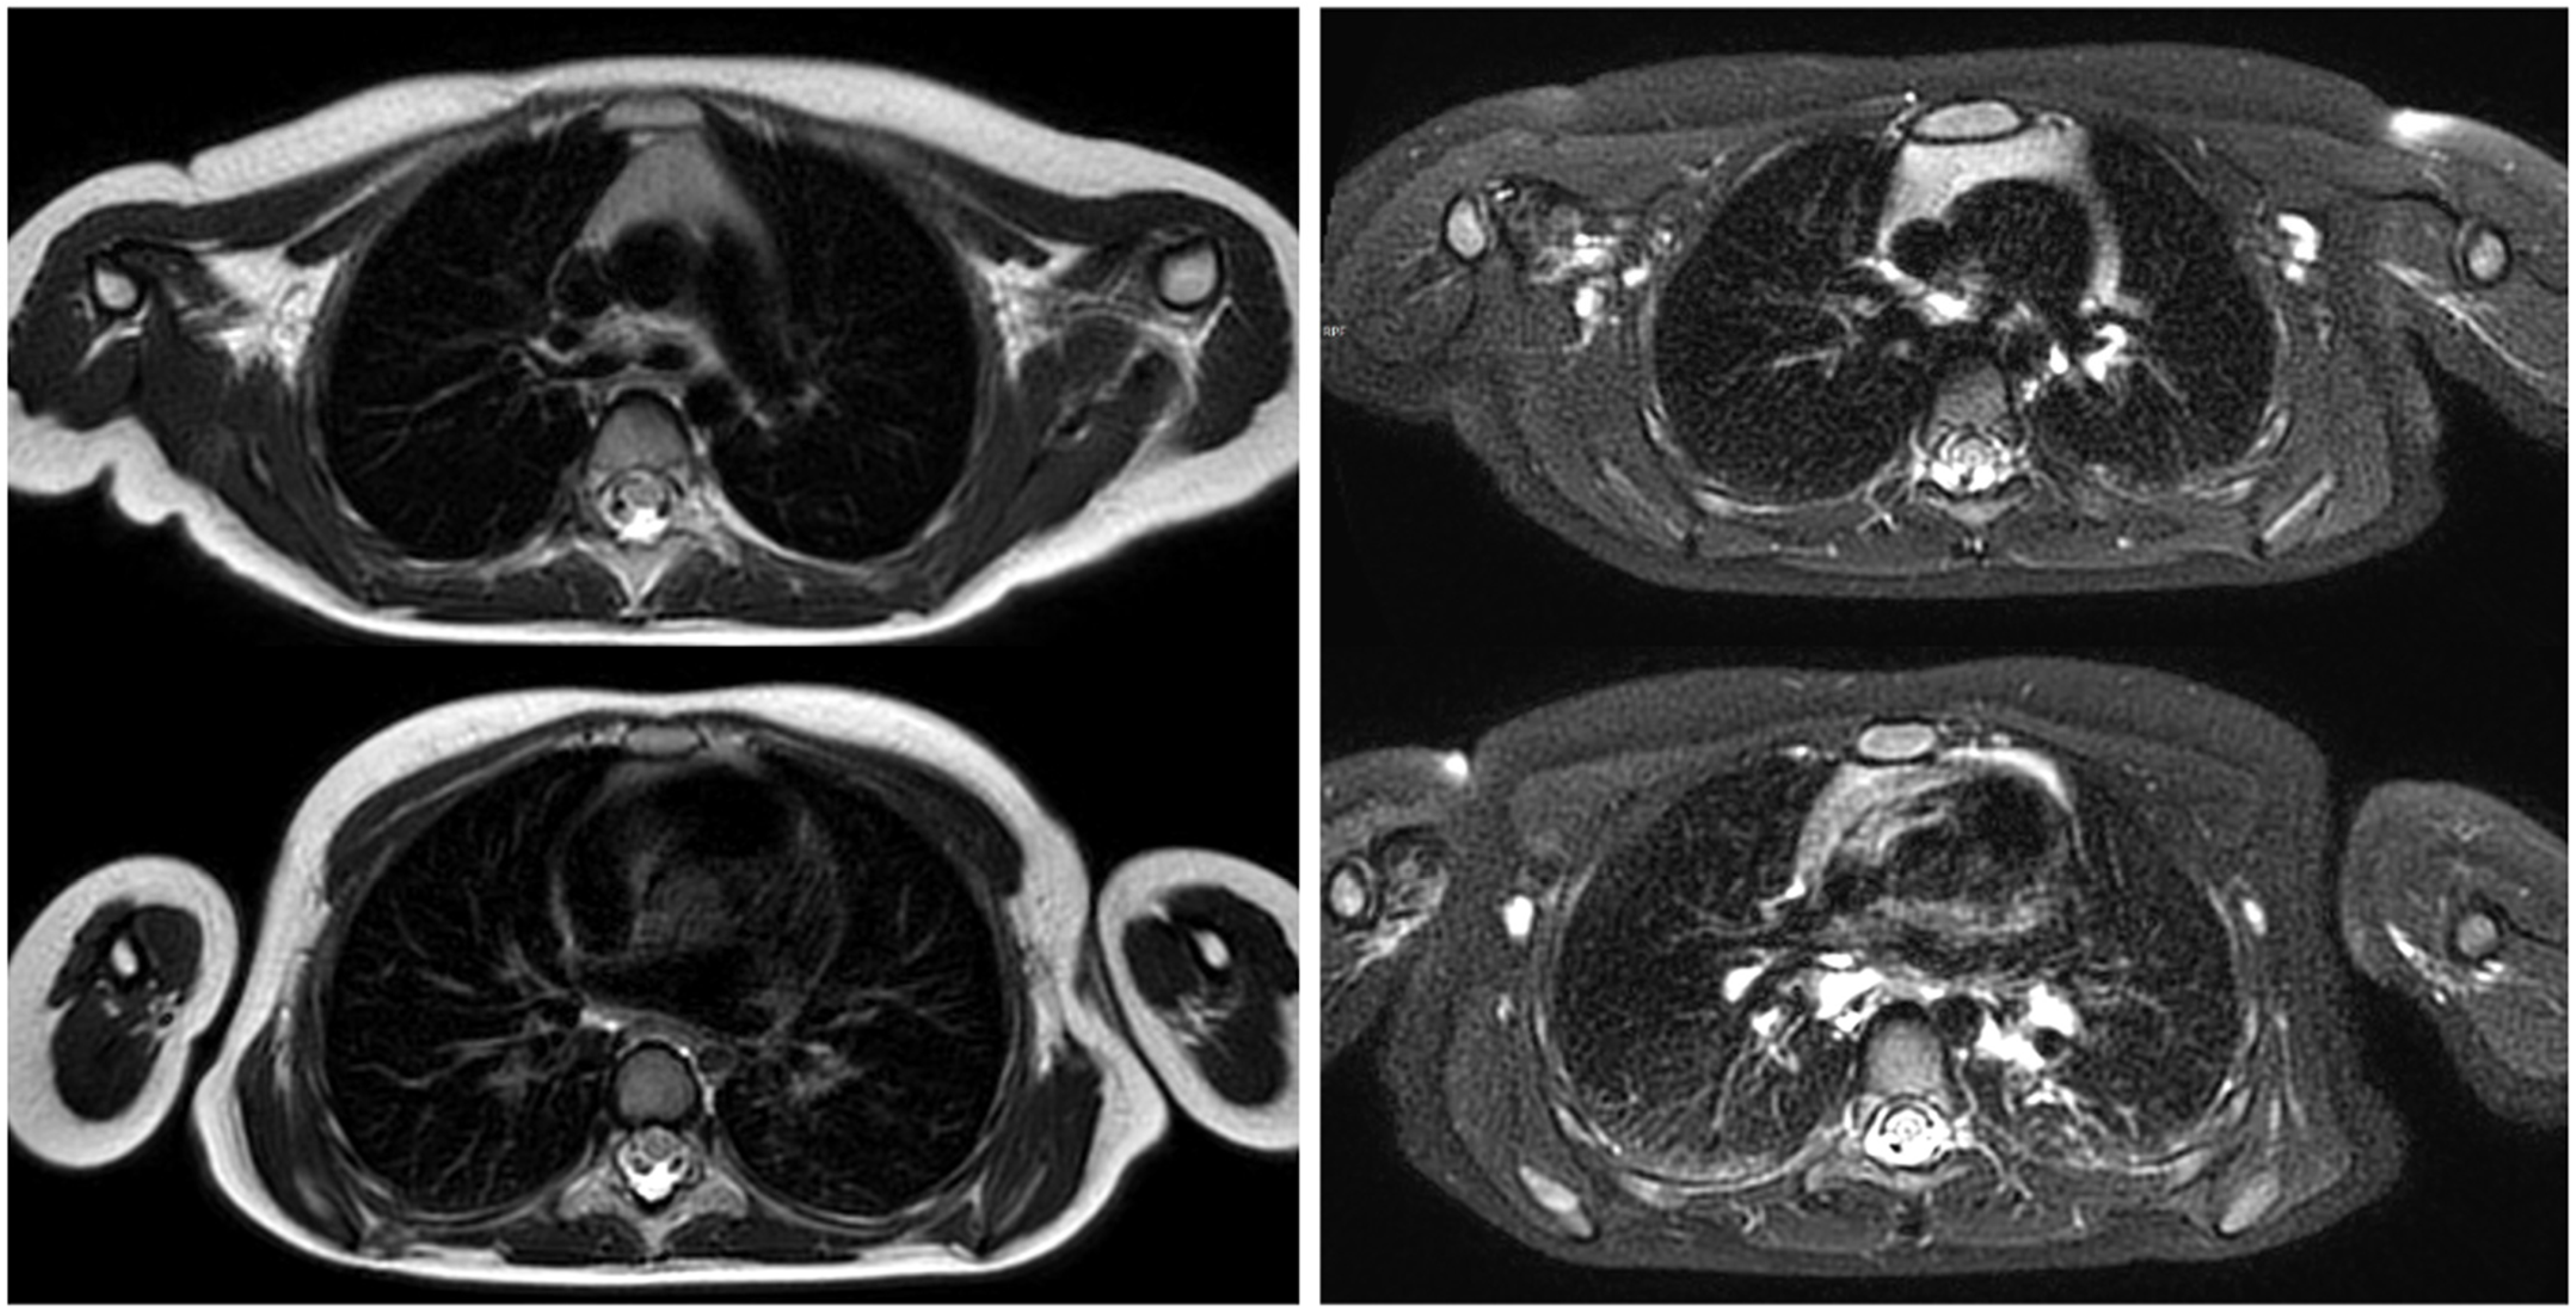

- Tischendorf, P.; Kunnemann, M.D.; Krahling, T.; Lange, J.H.; Heindel, W.; Beck, L. Thoracic MRI in Pediatric Oncology: Feasibility and Image Quality of Post-Contrast Free-Breathing Radial 3D T1 Weighted Imaging. Biomedicines 2025, 13, 2302. [Google Scholar] [CrossRef]